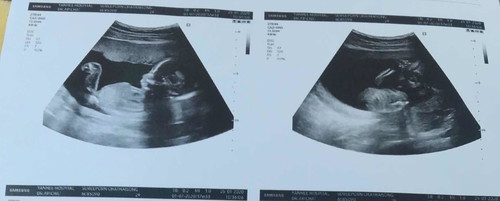

17w

นเองแข็งแรง ดิ้นเก่ง (น้องผู้ชาย) กำหนดคลอด 1 กรกฎาคม